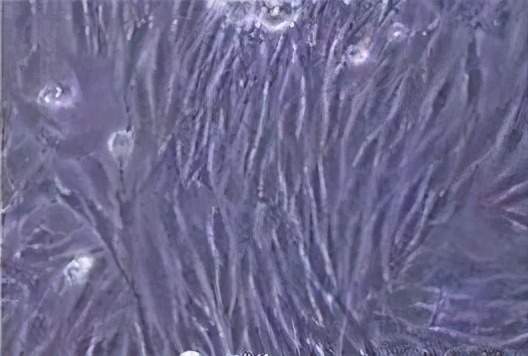

2、促进组织更新、修复与再生:

妇可馨通过在阴道的分解,其有效成分能够在抑制透明质酸酶的活性的同时,并能刺激纤维母细胞的生长与葡萄糖胺酶的合成,产生皮质酮类作用,促进肾上腺皮质激素的分泌,从而促进组织更新、修复与再生。